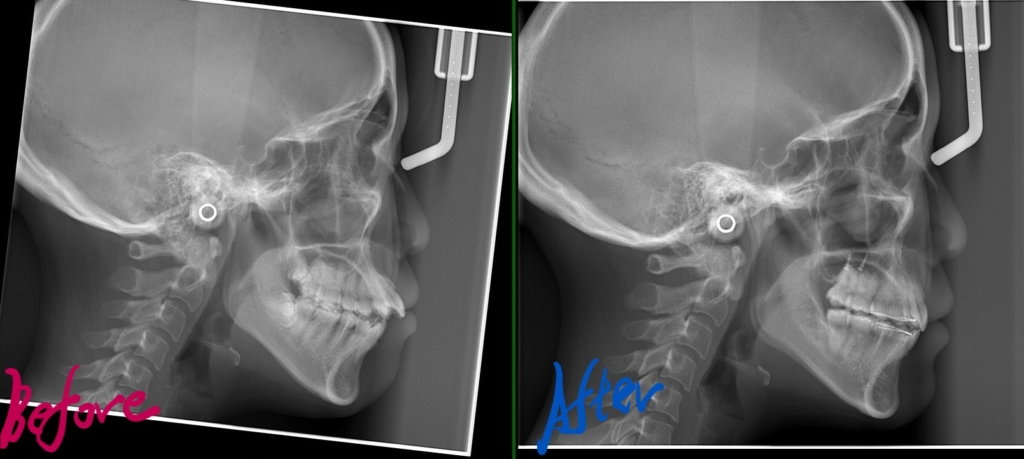

レントゲン写真でも矯正治療前後を比較してみましょう